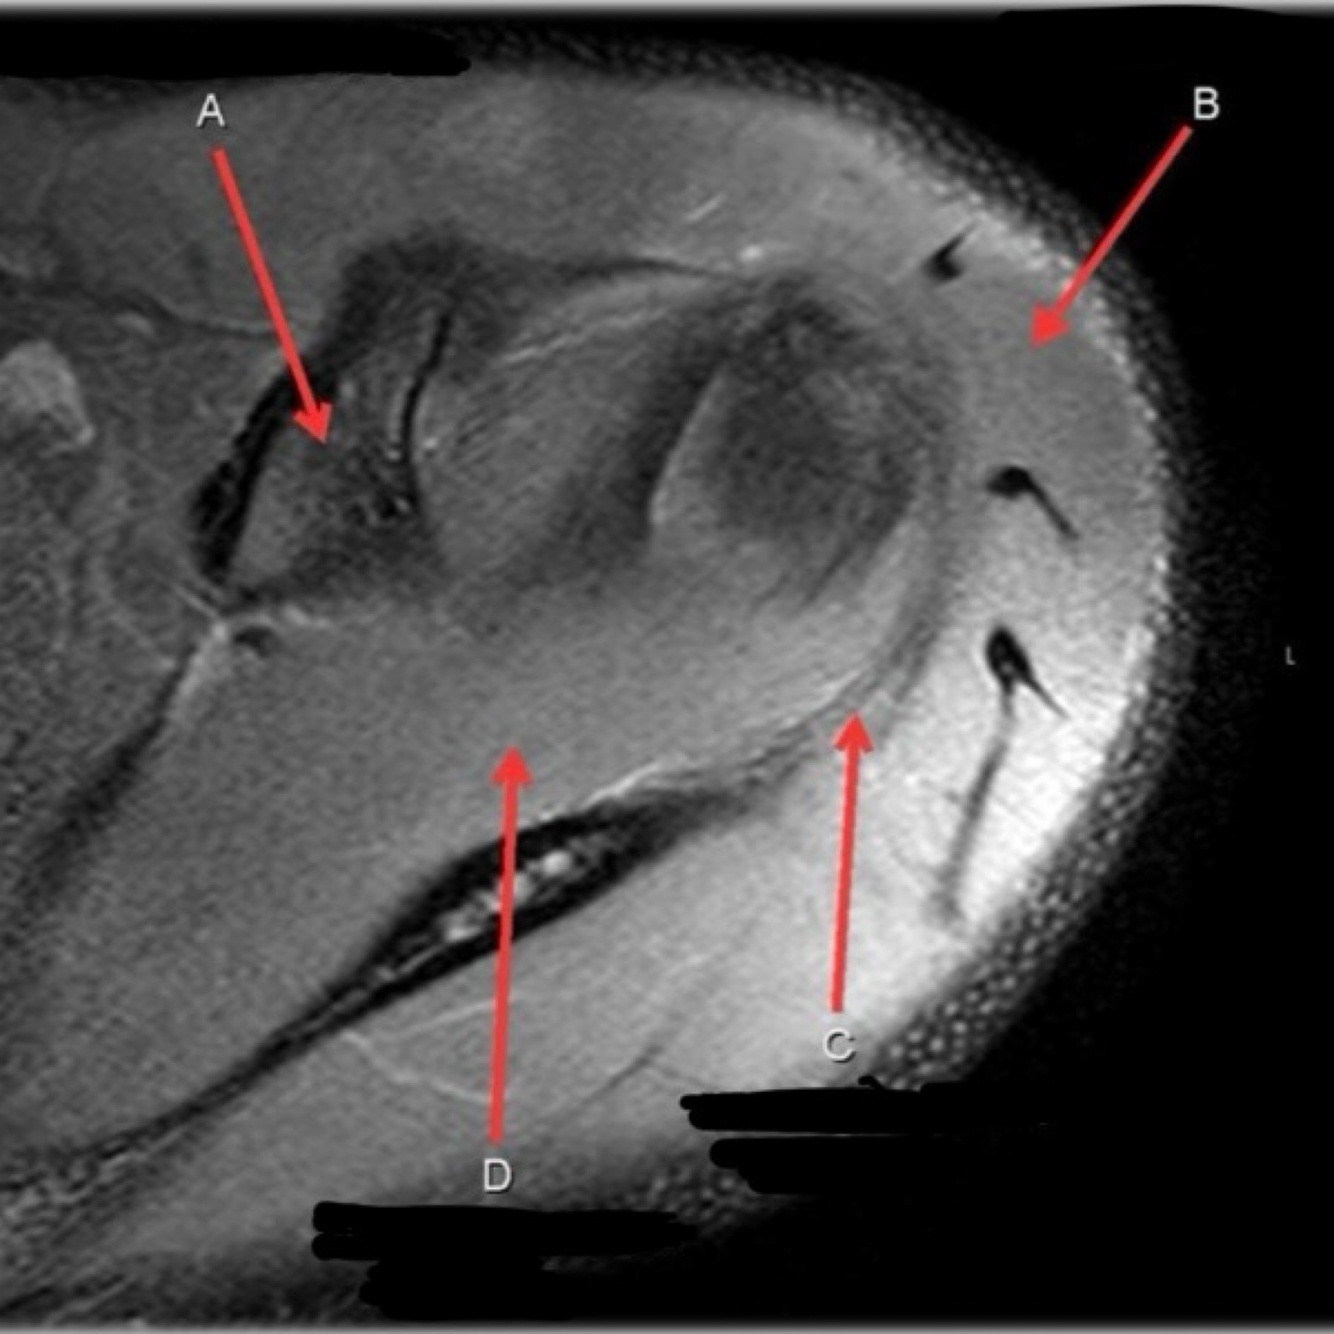

11

Q

What is letter A?

A

ANTERIOR LABRUM

How well did you know this?

1

Not at all

2

3

4

5